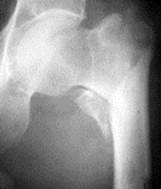

| Вколоченный перелом шейки бедра | Базальный(варусный) перелом шейки бедра | Чрезвертельный перелом бедра с отрывом малого вертела |